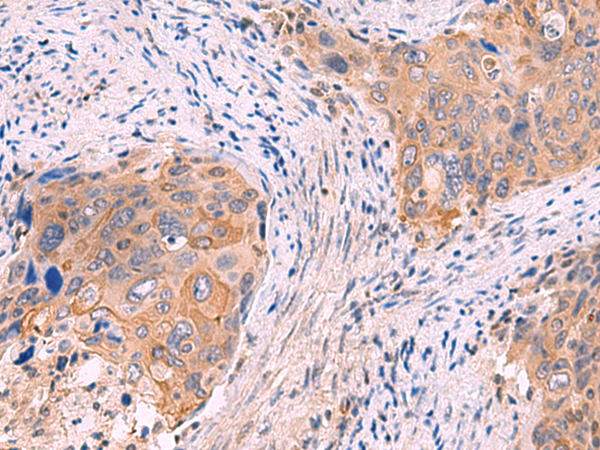

分类: 科研抗体货号: P10191别名: ANF1A2; HELIOS; ZNF1A2; ZNFN1A2应用: WB,IHC反应种属: Human, Mouse